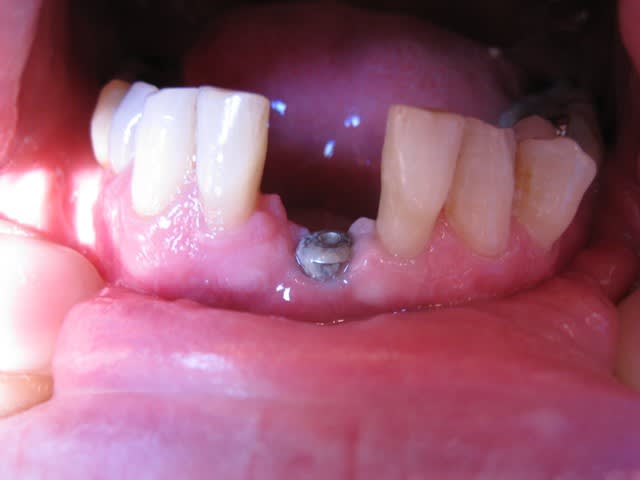

Hello

Un compromis pour remplacer 2 centrales 31-41

Voilà c'est mon 1er post !!

C'est un compromis, effectivement entre esthétique et hygiène et aussi la perte osseuse.

J'ai positioné l'implant là où l'os était car le patient ne souhaitait pas de greffe.

Donc je pensais à un système prothétique avec fausse gencive, soit transvissé ou scellé ! J'ai choisi scellé à cause de l'éventuelle sortie de vis.

Un pilier Procéra titane et un ensemble CCM avec céramique rose autorisant le passage du fil dentaire.

Sans cette fausse gencive, comment gérer les positions médiane et basse de l'implant/pilier proth. ?